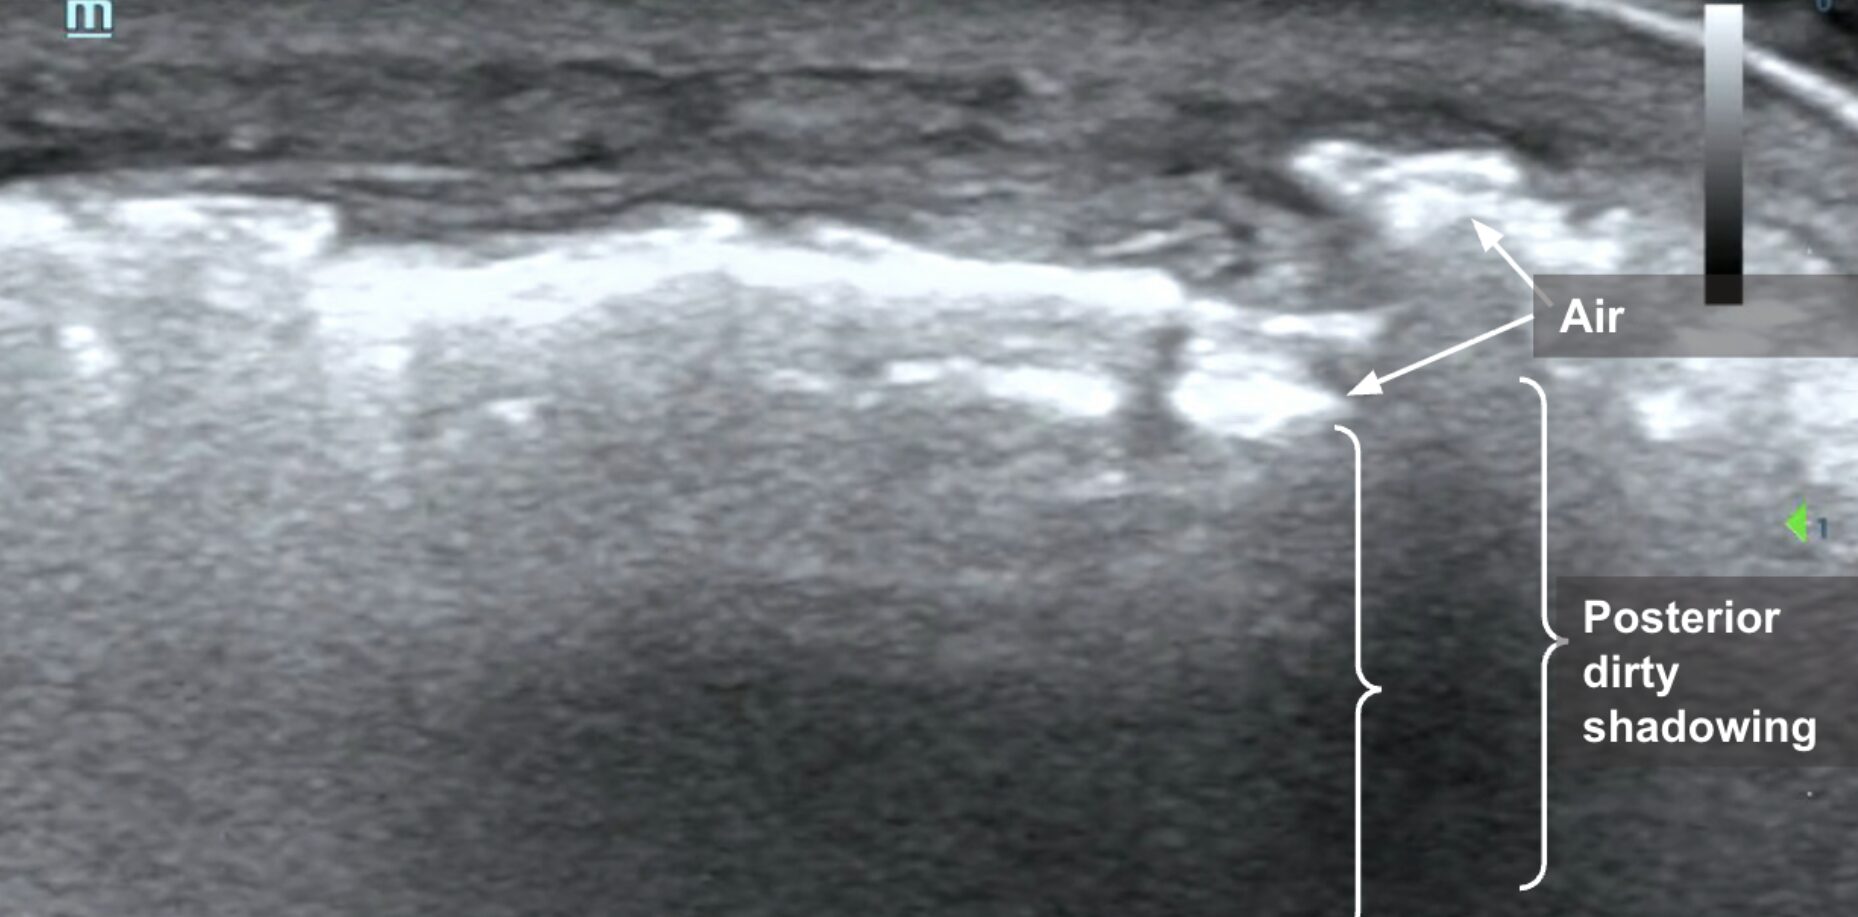

Subcutaneous emphysema on POCUS is demonstrated by hyperechoic foci with posterior “dirty shadowing” in the subcutaneous tissues. Since air scatters ultrasound beams, it results in a heterogeneous, speckled shadowing deep to the gas (Image 1, Image 2, Video 1).3 While subcutaneous emphysema is a key finding of necrotizing soft tissue infection (NSTI), it is also important to remember that it may be present in situations where there was dermal puncture that would introduce air into the soft tissue, such as in the case of animal bites or in the case of actively draining abscesses. In such clinical examples, subcutaneous air alone may not suffice to seal the diagnosis of NSTI.

Image 2: POCUS of the tibia in long-axis showing hyperechoic foci (arrows) with shadowing (brackets). Images courtesy of Dr. Shepherd and Dr. Alerhand.

Video 1: Linear transducer view of the tibia in long-axis demonstrating hyperechoic foci with shadowing scattered throughout subcutaneous layers.